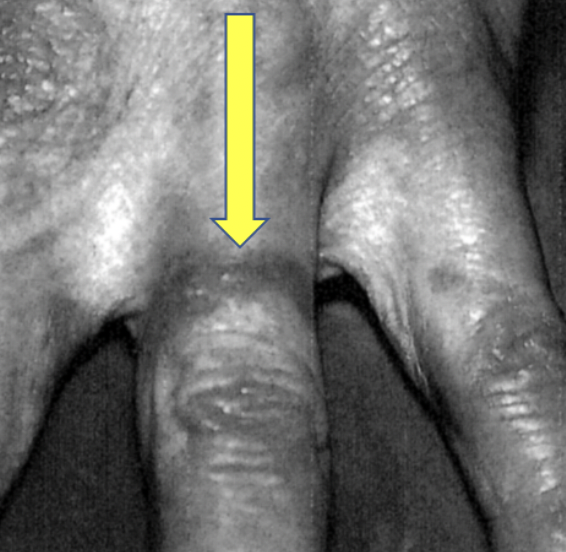

The effect of radioactive wedding rings on ring fingers was first documented in a 1967 JAMA paper by Simon and Harley. The authors reported that a husband and wife developed radiodermatitis on their ring fingers beginning shortly after their marriage 26 years earlier. And a 1968 JAMA letter reported a case of squamous cell carcinoma, which required amputation of the ring finger. There was even a wrongful death suit in 1983, which was thrown out.

Radiodermatitis from a wedding ring. Image: Miller and Aldrich, J Am Acad Derm, 1990;23:360-2.